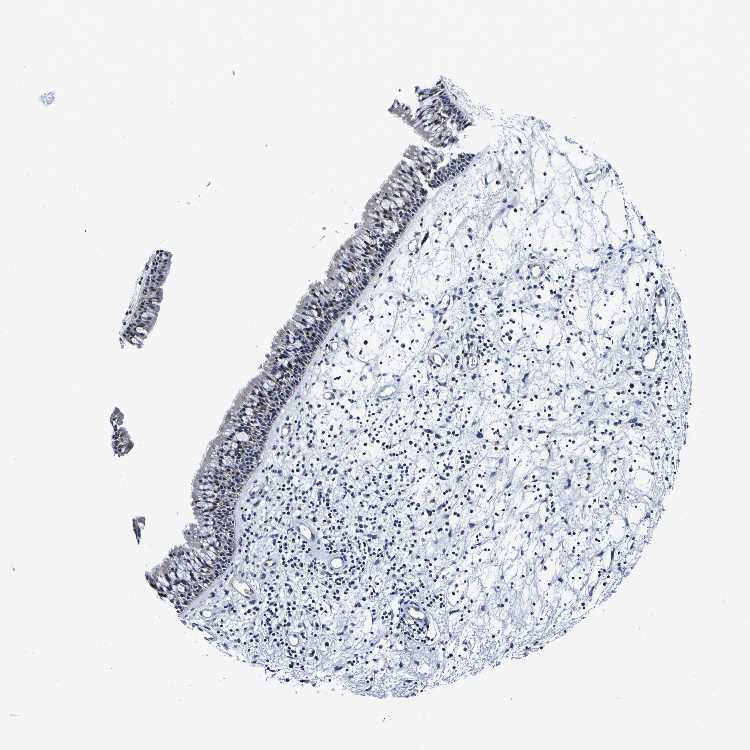

TISSUE PRIMARY DATA NASOPHARYNX Show tissue menu

NASOPHARYNX - Antibody stainingi

Antibody staining in the annotated cell types in the current human tissue is reported as not detected, low, medium, or high, based on conventional immunohistochemistry profiling in selected tissues. This score is based on the combination of the staining intensity and fraction of stained cells.

Each image is clickable and will lead to virtual microscopy that enables deeper exploration of all samples and also displays staining intensity scores, fraction scores and subcellular localization as well as patient and tissue information for each sample.

Antibody HPA011912

Respiratory epithelial cells Medium